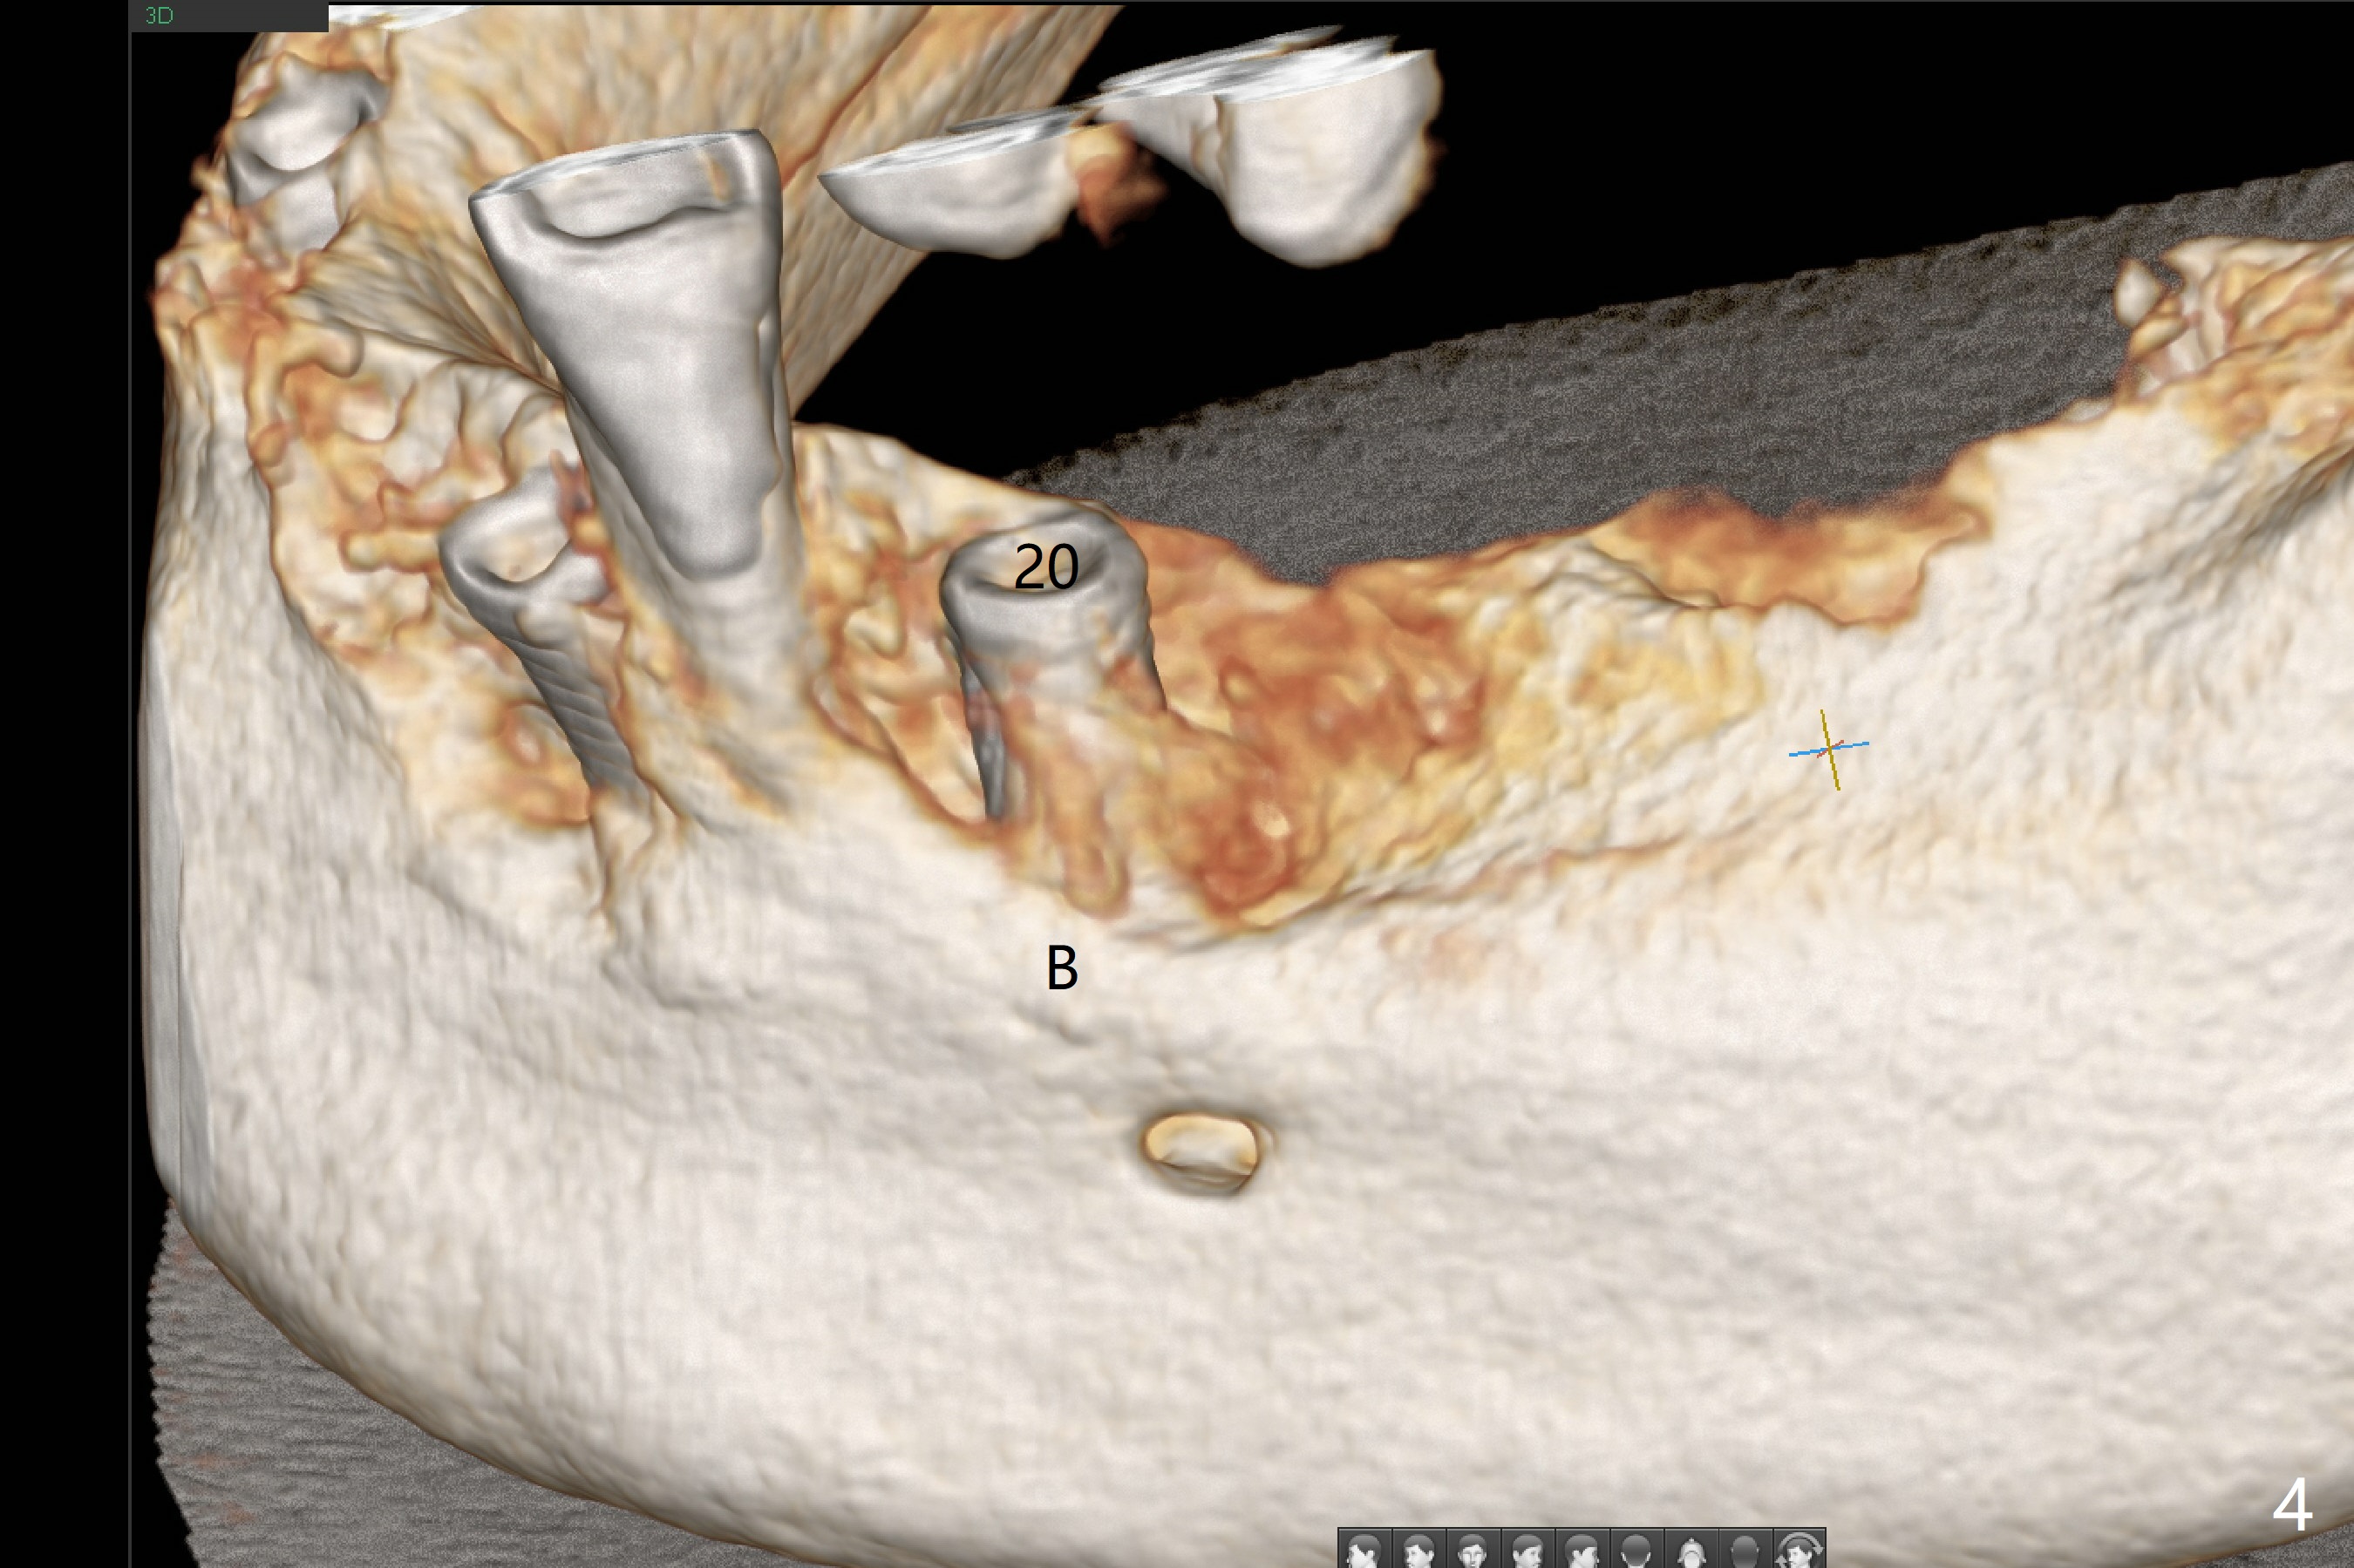

Three months post socket preservation (with buccal plate loss previously), a 3.5x11.5 mm implant is placed at #27 subcrestal (Fig.1). When implants are placed at #22 and 20 (Fig.2,4), threads are exposed buccal (B). Mixture of autogenous bone and allograft is placed to cover the exposed threads (Fig.3,5) following deep placement at #20. For safety, the implant at #20 is buried. Pain control at #18 is poor when initial osteotomy is being established (Fig.6 *), as related to severe infection. Repeated block anesthesia allows to finish implant placement with primary stability; a 3.5x2 mm ball abutment is placed (Fig.7). With placement of 2 other ball abutments at #27 and 22 (Fig.3), the lower existing RPD is converted to a removable provisional (Fig.8). With addition of acrylic, the socket of #20 is covered (Fig.9). There is no apparent bone #20 distal 3 months postop (Fig.10,11 <). Re-graft is needed? The implant at #21 appears immediately subgingival 5 months postop (Fig.12 *). The distobuccal threads are exposed (Fig.13). After decortication, allograft is placed, followed by 6-month membrane. In fact, a shorter and smaller implant should be placed instead. The patient has to wear the RPD for mastication. It would be more painful without it. Later the tissue surface of the RPD is trimmed.